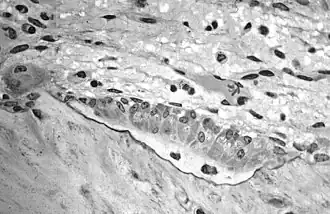

In histology, osteoid is the unmineralized, organic portion of the bone matrix that forms prior to the maturation of bone tissue.[1] Osteoblasts begin the process of forming bone tissue by secreting the osteoid as several specific proteins. The osteoid and its adjacent bone cells have developed into new bone tissue when it becomes mineralized.

Osteoid makes up about fifty percent of bone volume and forty percent of bone weight. It is composed of fibers and ground substance. The predominant type of fiber is type I collagen and comprises ninety percent of the osteoid. The ground substance is mostly made up of chondroitin sulfate and osteocalcin.